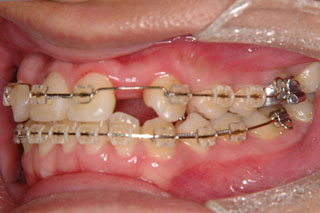

下顎前突が見られます。上顎の左右の側切歯(2番目の歯)は先天欠如でした。最近まで左上の乳犬歯が残っていた跡が見られます。下の歯は叢生も見られません。先欠の対応では素直に考えて人工的に歯を補う補綴処置が第一選択肢になります。矯正治療では、しばしば抜歯を行う事が多いので、先欠が在れば、その他の歯を抜歯して解決する事も多いですが、この方の場合は非抜歯の計画に致しました。

非抜歯での治療になりましたので、上顎の中切歯と犬歯の間に側切歯のスペースを作っている所です。もともと歯が無かったために、前方にも側方にも歯槽骨が少なく傾斜移動が多いので慎重な移動が求められます。

使用した主な装置名:マルチブラケット装置

抜歯/非抜歯および抜歯部位:非抜歯

治療期間:動的処置2年6か月、経過観察3年